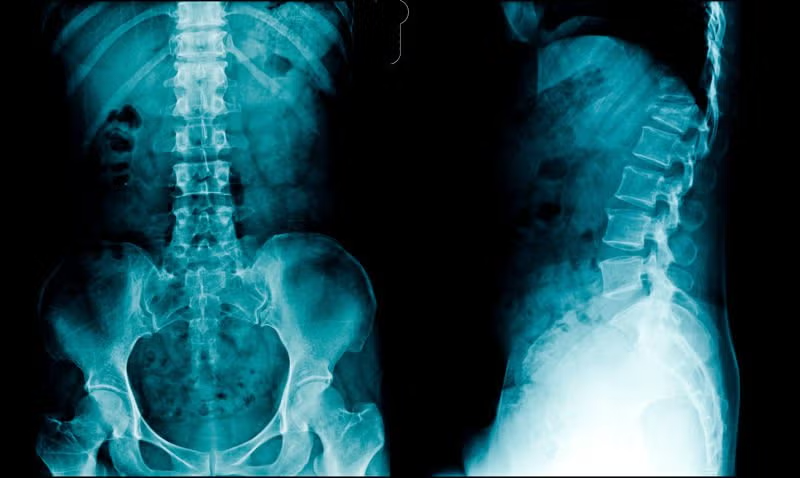

La radiografía simple en el estudio del dolor de la columna vertebral

Sin embargo, la radiografía simple aún sigue siendo ampliamente utilizada en atención primaria y especializada. Por tanto, se mantiene vigente el conocimiento de la anatomía radiológica normal y de las manifestaciones radiológicas de los distintos procesos patológicos que afectan a la columna vertebral y que pueden ser responsables del dolor vertebral.

El objetivo de este trabajo es realizar una revisión general de las manifestaciones en la radiografía simple del amplio espectro de patologías que pueden ser responsables del dolor generado en la columna vertebral. Este espectro abarca la patología congénita, traumática, degenerativa, tumoral, inflamatoria e infecciosa.